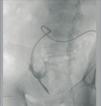

Case 2. 65-year-old woman who started PD after a second transplant. During surgery for the catheter placement, multiple intestinal adherences are freed. From the start, infusion went without difficulty, but drainage was impossible. A catheterography confirmed the suspicion of entrapment; the catheter was then removed through surgery (Figure 2).

Figure 2. Case 2